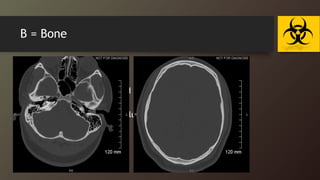

B = Bone

• Examine by bone window :

• fractures

• evaluate the sinuses for fluid or soft tissues accumulation

• Mastoid air cell

• Fluid in the sinus may be a clue to a facial injury !!

B = Bone •Examine by bone window : • fractures • evaluate the sinuses for fluid or soft tissues accumulation • Mastoid air cell • Fluid in the sinus may be a clue to a facial injury !!